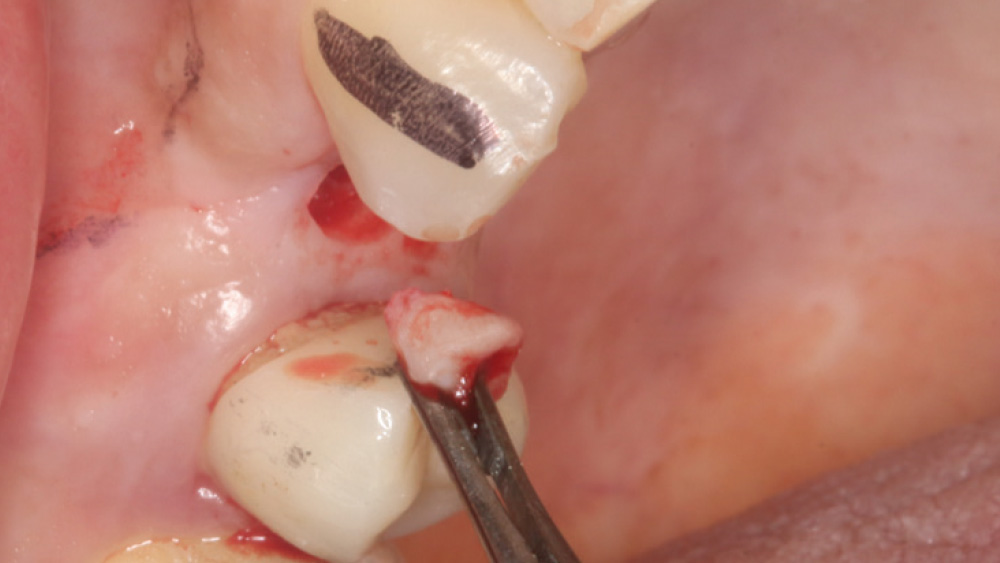

When the attached tissue is minimal, a flap procedure allows the surgeon to reposition the flap to create more attached gingiva and improve the interdental papillae at the implant site. Reflecting a gingival flap also enables the practitioner to more clearly see the final position of the implant at the crest of the bone. If it’s necessary to visualize the bone during the surgical procedure due to uncertain ridge width or height, flap reflection is the safest, most predictable approach.

CASE REPORT

The following case, which I performed alongside Dr. Stephanie Tilley of Pensacola, Florida, illustrates the use of both surgical techniques for the same patient, who presented with edentulous spaces in the areas of both right and left maxillary first bicuspids. Due to varying soft-tissue volume on each side of the arch, implant surgery was performed using a flapless procedure for one site, while the attached gingiva was reflected to expose the available hard tissue for the other. As a result of proper site evaluation, treatment planning and restorative-driven implant placement, both surgical techniques led to successful outcomes for the patient.